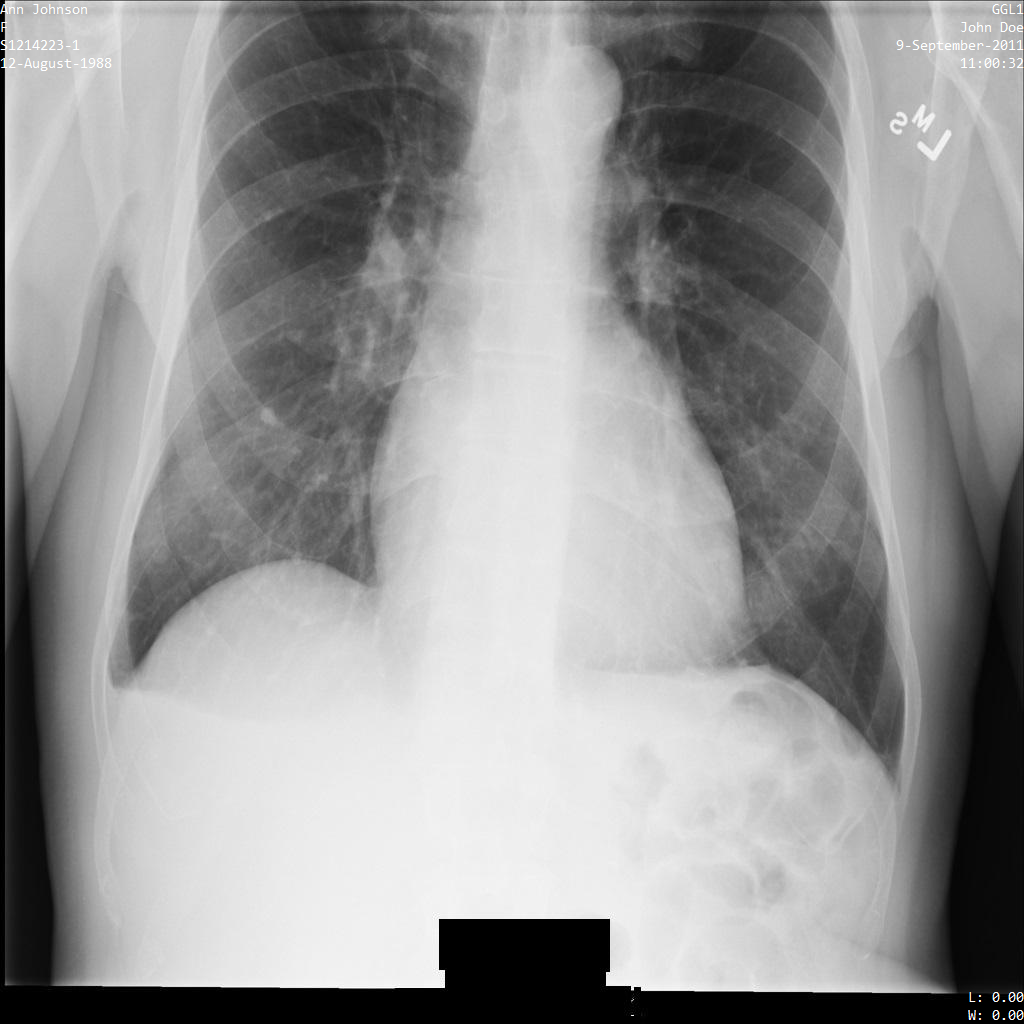

다음 각 섹션에서는 다양한 방법을 사용하여 DICOM 데이터를 익명화하는 방법을 설명합니다. 익명화된 이미지의 출력은 각 샘플에 제공됩니다. 각 샘플은 다음과 같은 원본 이미지를 입력으로 사용합니다.

각 익명화 작업의 출력 이미지를 이 원본 이미지와 비교하여 작업의 효과를 확인할 수 있습니다.

Cloud Healthcare API에 이미지를 제출하면 이미지가 다음과 같이 표시됩니다. 이미지 상단 모서리에 표시되는 메타데이터가 수정되었지만 이미지 하단에 있는 번인 보호 상태 정보(PHI)는 유지됩니다. 번인 텍스트도 삭제하려면 이미지에서 번인 텍스트 수정을 참조하세요.

REST